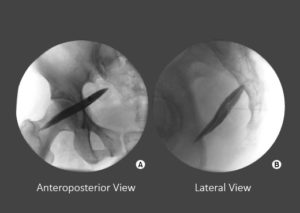

Your doctor uses a type of X-ray called fluoroscopy to guide a needle like instrument to the nerve connected to the damaged joint. The doctor injects local anesthetic to numb the nerve. Next, you compare your pain levels before and after the LA. If the injections reduce your pain, you are the right candidate for this wonderful procedure ie radiofrequency facet denervation.

Name of these tiny nerves is medial branch. Except sending pain signals to brain, these nerves do not have any other utility, so can be safely targeted.